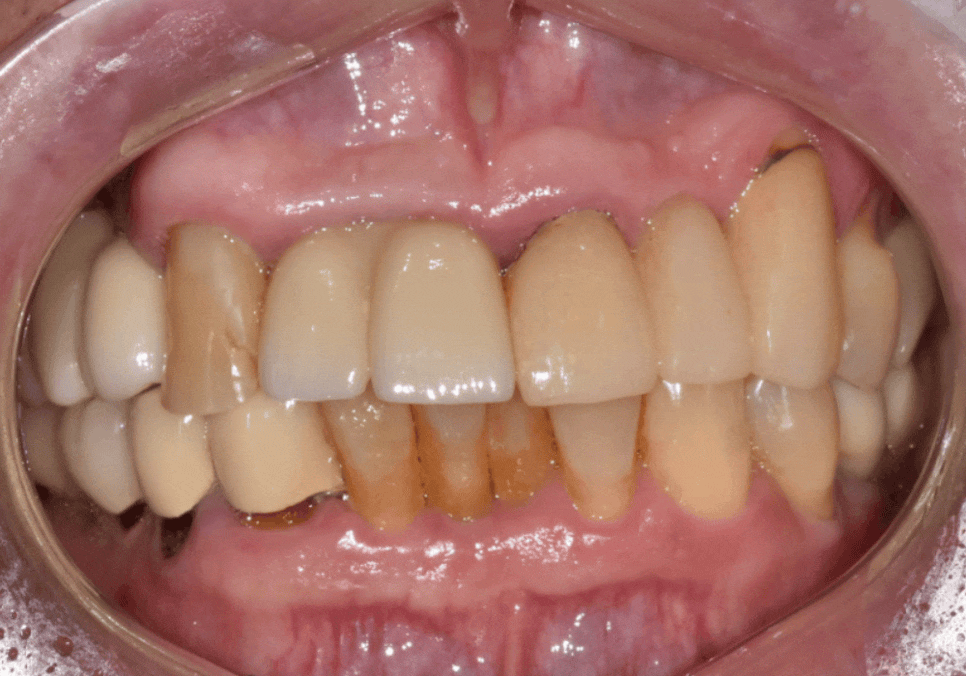

브릿지 제거 후 그 안을 살펴보니...

음식물 끼임, 거뭇한 무언가 보인다면? 이미 늦었을 수 있습니다.

기존 브릿지를 제거하고

내부 상태를 확인했습니다.

예상대로 음식물 찌꺼기와 오염이 심각했지만,

여기서 불행 중 천만다행인 사실...

230516

남은 치아의 양이 적당하여

발치는 피할 수 있는 상황이었어요.

저는 환자분께 기존의 연결된 형태가 아닌,

각각의 치아를 독립적으로

치료하는 방식을 제안 드렸습니다.

만약 다시 브릿지로 제작한다면,

추후 한 치아에만 문제가 생겨도

연결된 모든 보철물을 제거해야 하는

위험 부담이 있기 때문이죠.

따라서 장기적인 유지 관리의 효율성을 위해

다음과 같이 계획을 세웠습니다.

신경치료를 진행한 후

단단한 지르코니아 크라운을 씌우고,

잇몸 뼈가 튼튼하여 '뼈이식 없이'

임플란트를 식립하기로 했습니다.

우식 부위만 깨끗이 제거한 뒤

지르코니아 크라운으로

마무리하기로 결정했습니다.